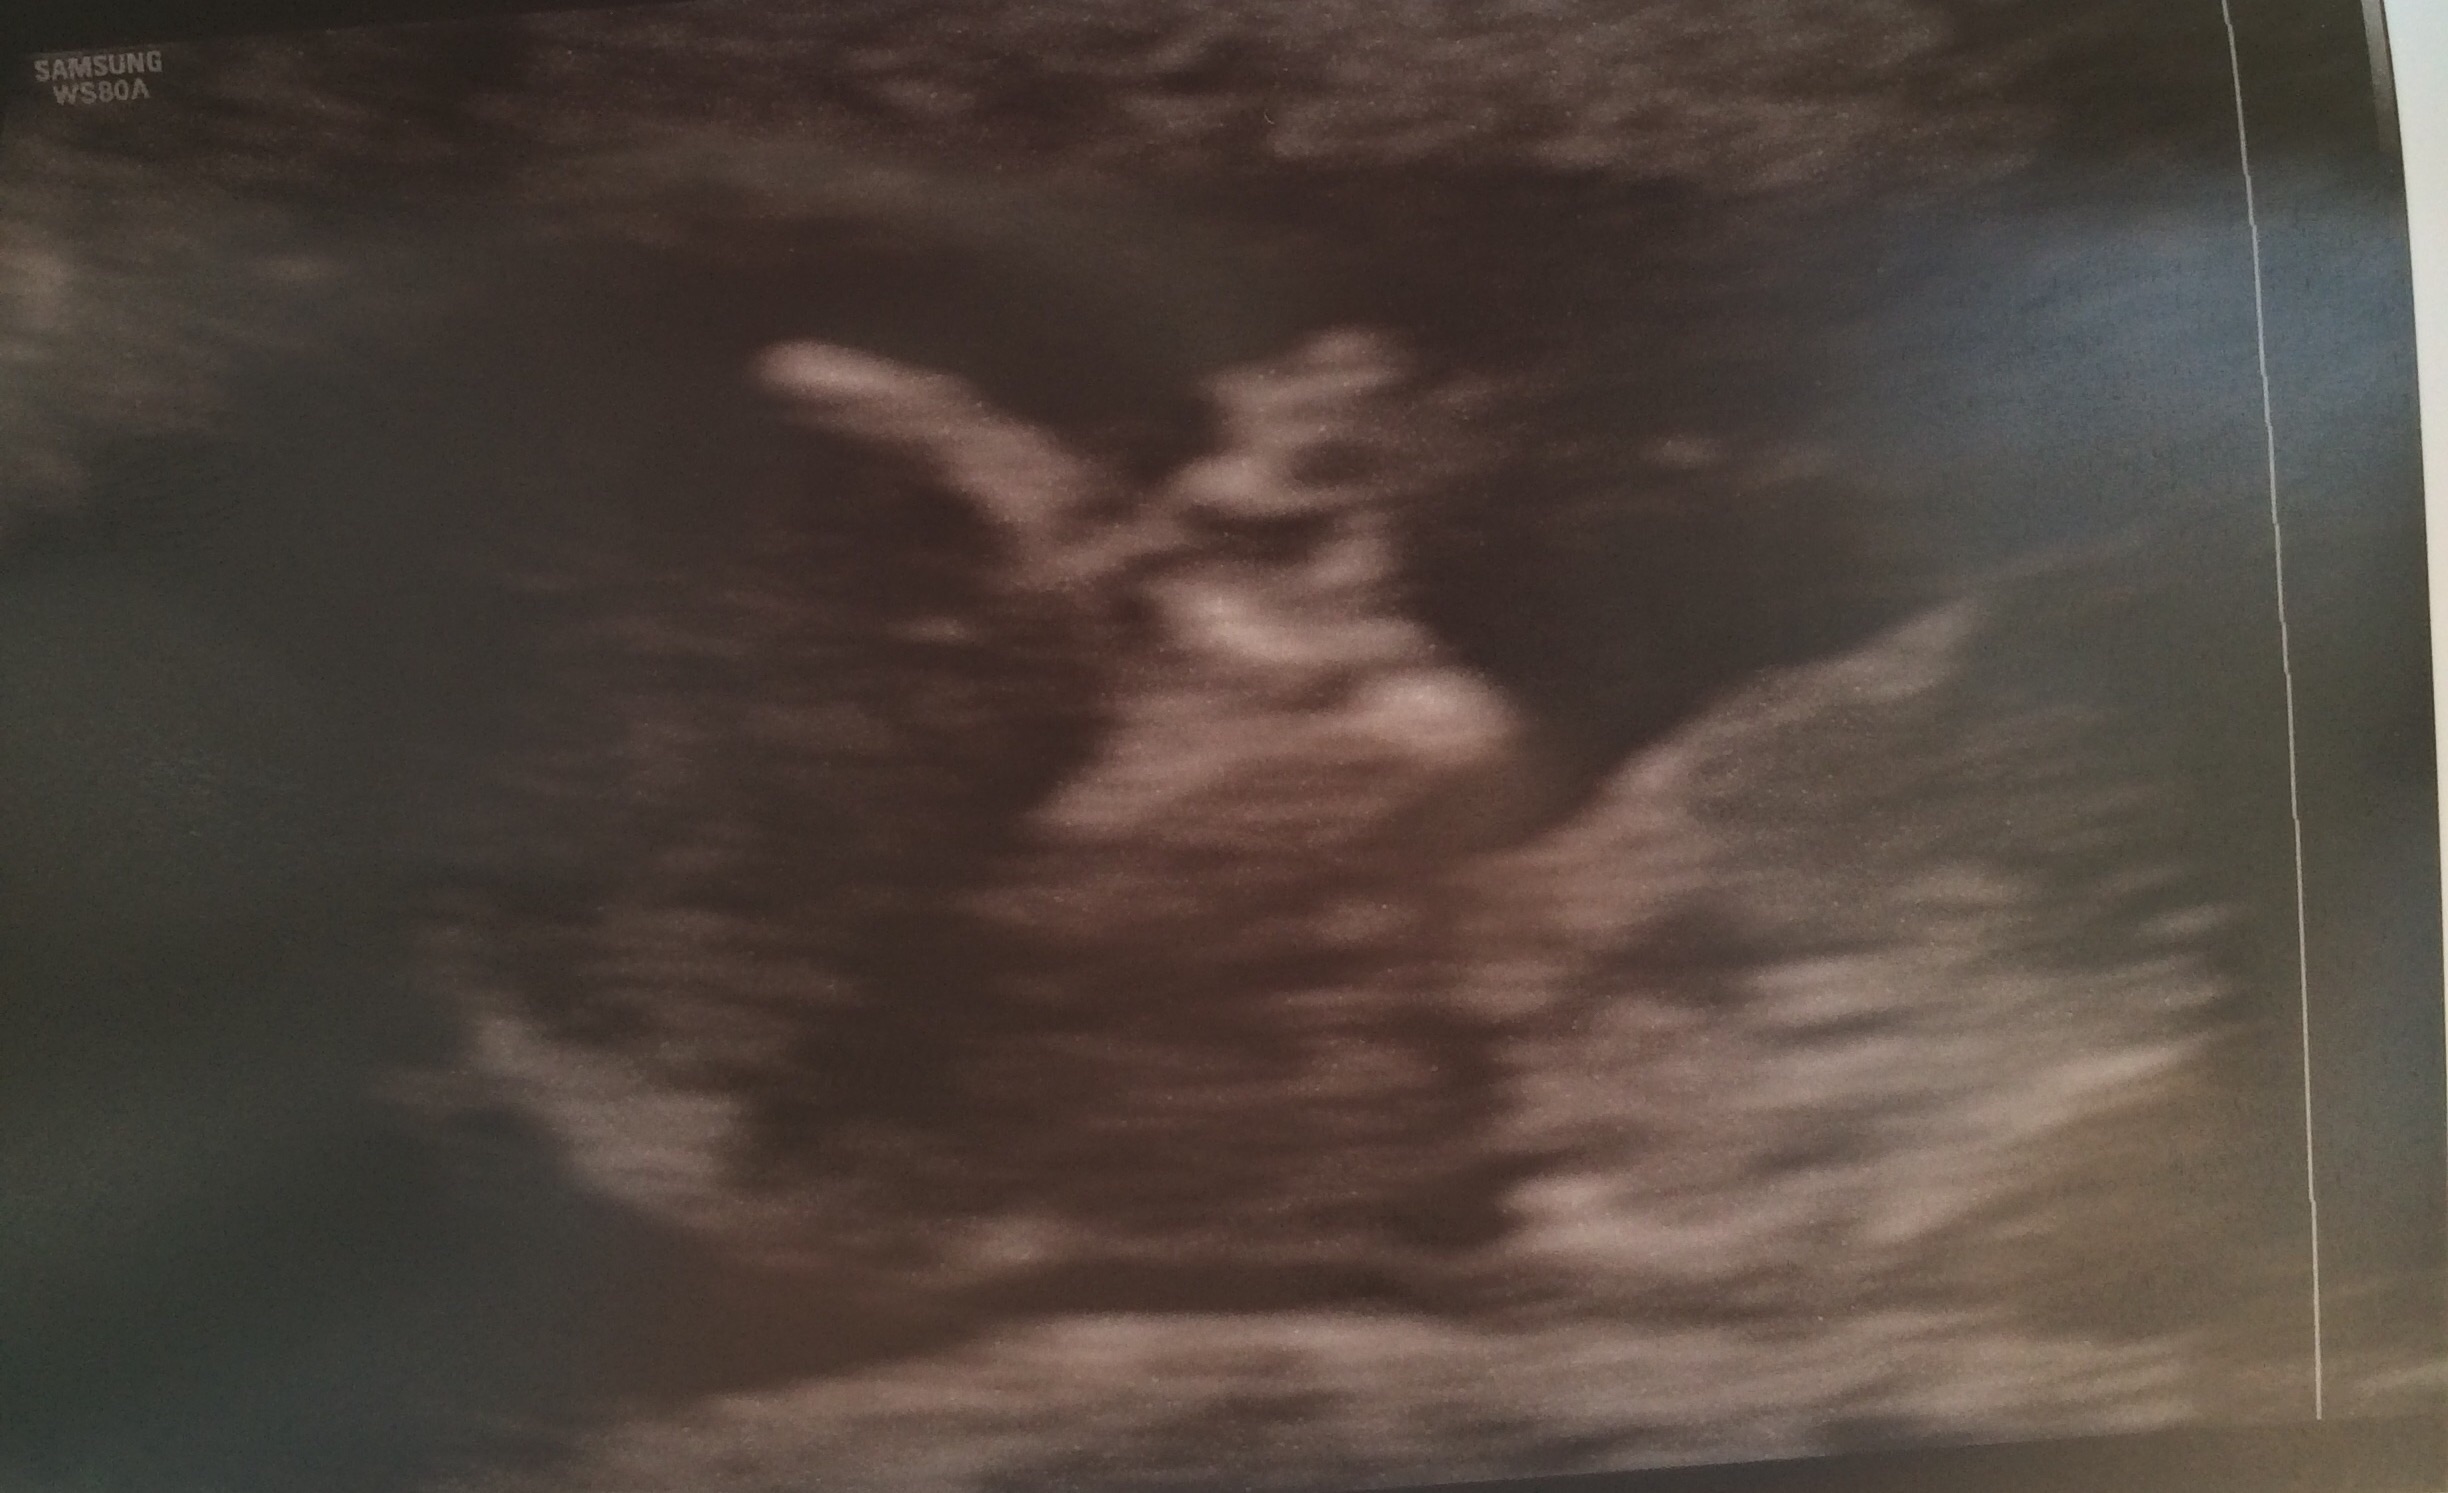

Here are my twins from my 13 week ultrasound. Both have strong heartbeats! One measuring at 13 weeks 4 days and the other 13 weeks 6 days. Tech made a guess and thinks they're boys!!